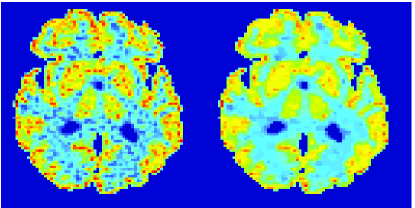

In figures 3 and 4 we illustrate the uptake rates and relative error in the uptake rates, respectively, calculated by Patlak, TV-Patlak, Patlak-GF and Patlak-MF for one simulated data case , i.e. , noise in the input function and Poisson noise in the sinograms. The uptake rate image generated by Patlak-MF is visually smoother than that by TV-Patlak, but the equivalent histograms show that the relative error is higher for Patlak-MF than for TV-Patlak; the Patlak-MF image is over-smoothed.